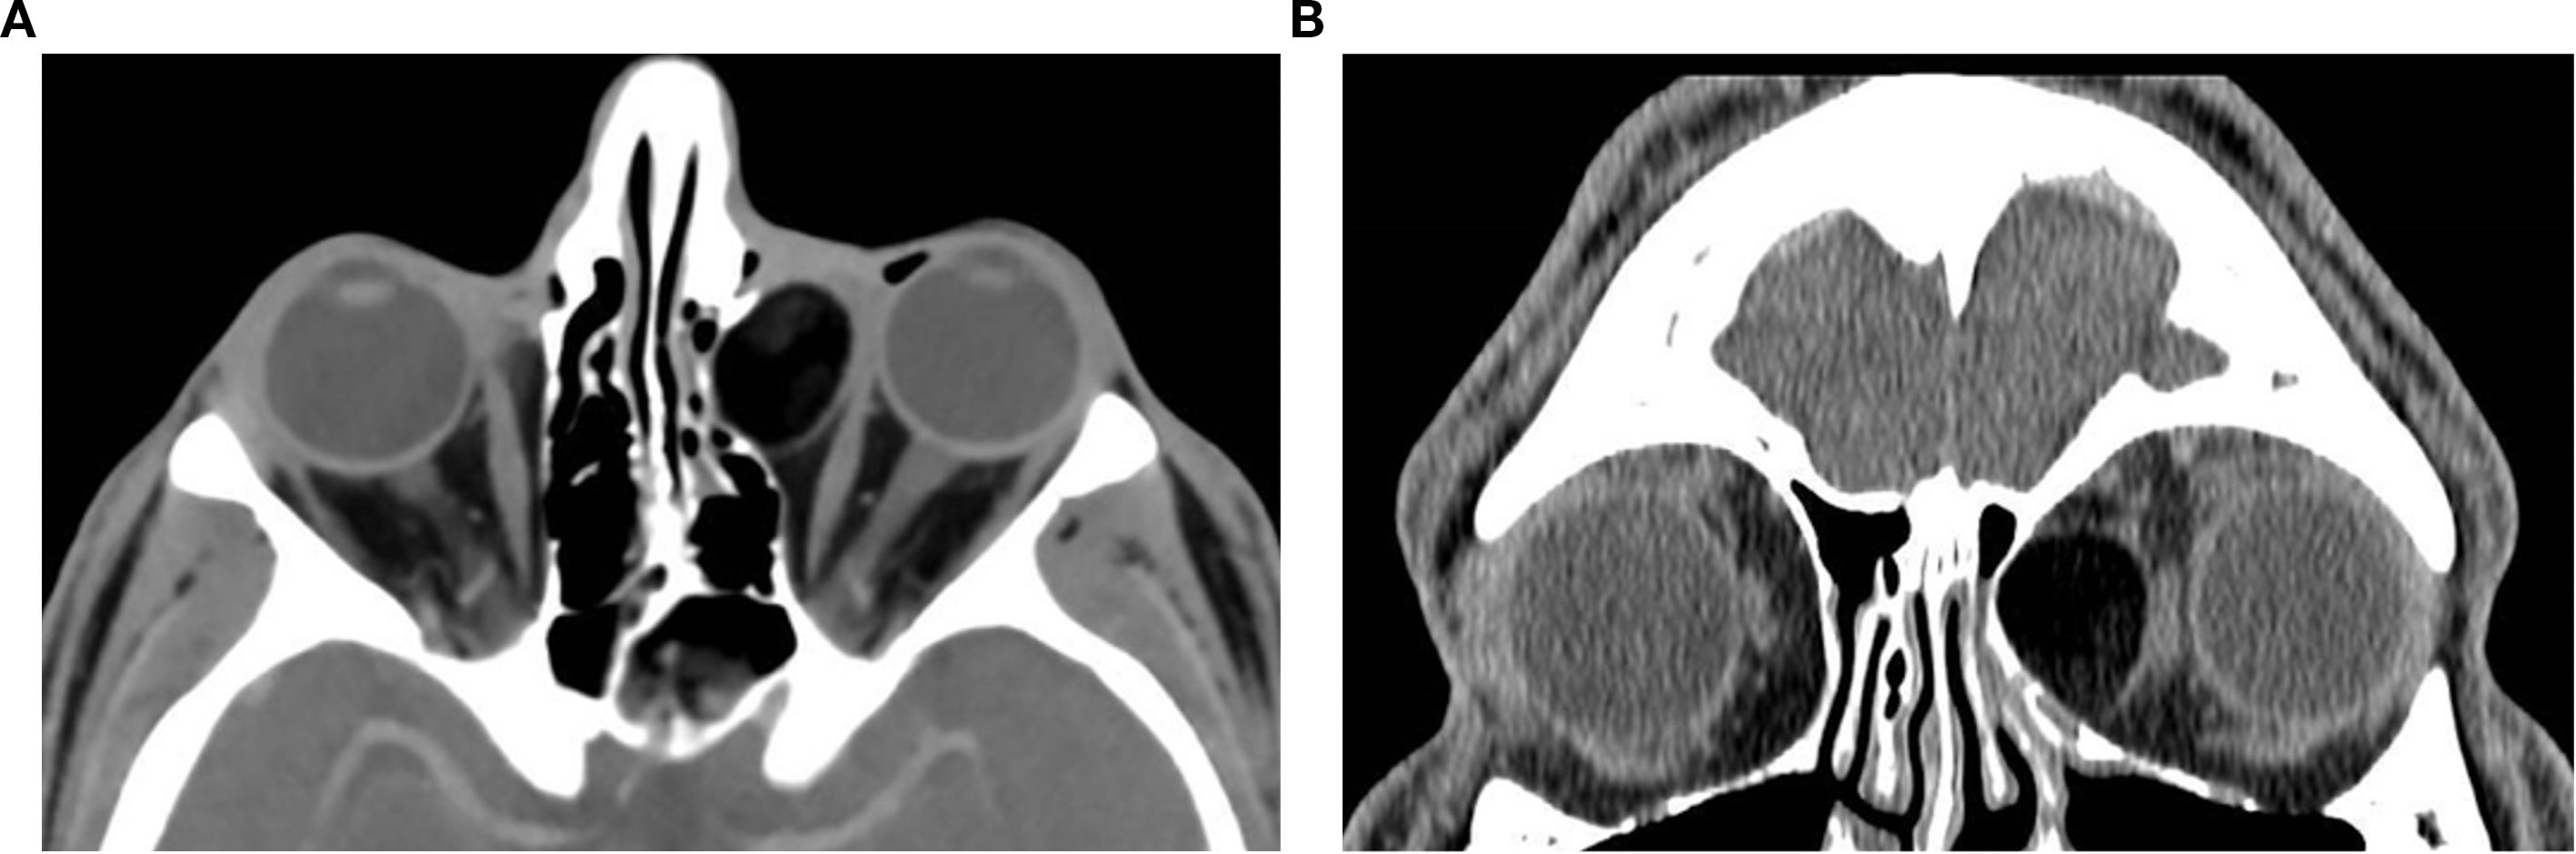

Orbital masses include a diverse spectrum of benign, malignant, inflammatory, and vascular lesions in pediatric and adult patients. Accurately diagnosing the type of lesion is critical, as management strategies differ significantly. Advanced imaging is therefore essential, and computed tomography (CT) is central to orbital evaluation. We reviewed the literature to synthesize evidence on CT features across common orbital pathologies and correlated imaging with clinical presentation to emphasize diagnostic relevance. CT characteristics are summarized for vascular lesions (cavernous venous malformation, lymphatic malformation), inflammatory conditions (orbital myositis, dacryoadenitis), benign lesions (dermoid cyst, pleomorphic adenoma), and malignant lesions (lacrimal gland lymphoma, adenoid cystic carcinoma, rhabdomyosarcoma). We present characteristic patterns of location, morphology, enhancement, and bone change, with practical discriminators and common pitfalls to aid differentiation. When used alongside clinical context, CT remains a preferred modality in many clinical settings due to its rapid acquisition, wide availability, and reliable depiction of bone and calcifications. It supports accurate diagnosis and informed management decisions in time-critical settings. This review provides a structured reference for interpreting CT findings across a wide range of orbital disease.